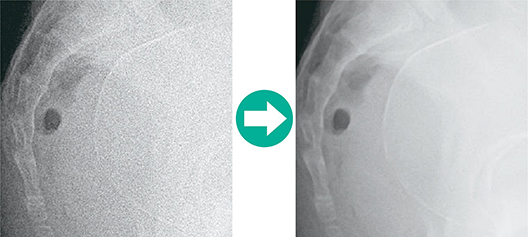

Although this is a compact machine its excellent image quality is the same as that produced by the rest of the FCR range. Image Intelligence™, Fujifilm's proprietary image processing technology, enhances image contrast and sharpness, without any deterioration of details. FCR PRIMA T supports accurate diagnosis by offering stable and optimized image quality.

Enhances FCR images. All diagnostic scopes will be enhanced except for noise.

Provides a non-grainy image by mainly isolating and suppressing the noise for the signal.